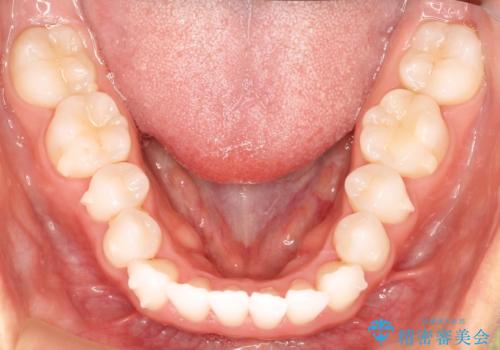

気になる前歯の歯並びをインビザラインで矯正

- 前歯の傾きと、ガタガタが気になるとのことで来院されました。

前歯の傾きや高さをシミュレーションで患者様と確認しながら、歯並びを仕上げていきました。

遠方での合宿などで長期に来院できない場合も、インビザラインなら治療が可能となります。